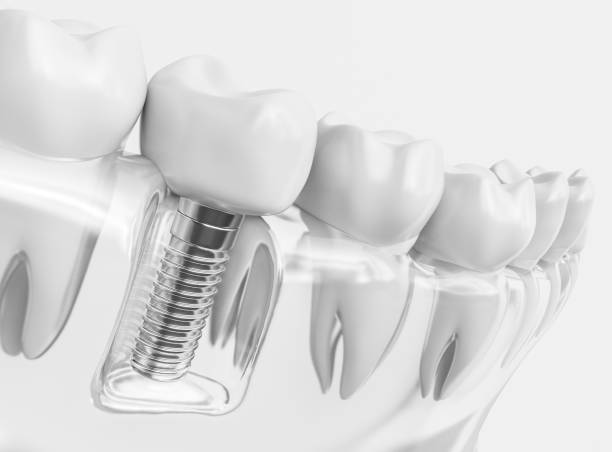

Våra tandimplantat är en hållbar lösning för att ersätta förlorade tänder. Genom en skicklig och skonsam procedur återskapar vi ditt leende och din tuggförmåga. Med modern teknik och erfarenhet erbjuder vi kvalitetsimplantat för långsiktig oral hälsa. Återfå ditt självförtroende och funktionalitet med våra tandimplantat idag!